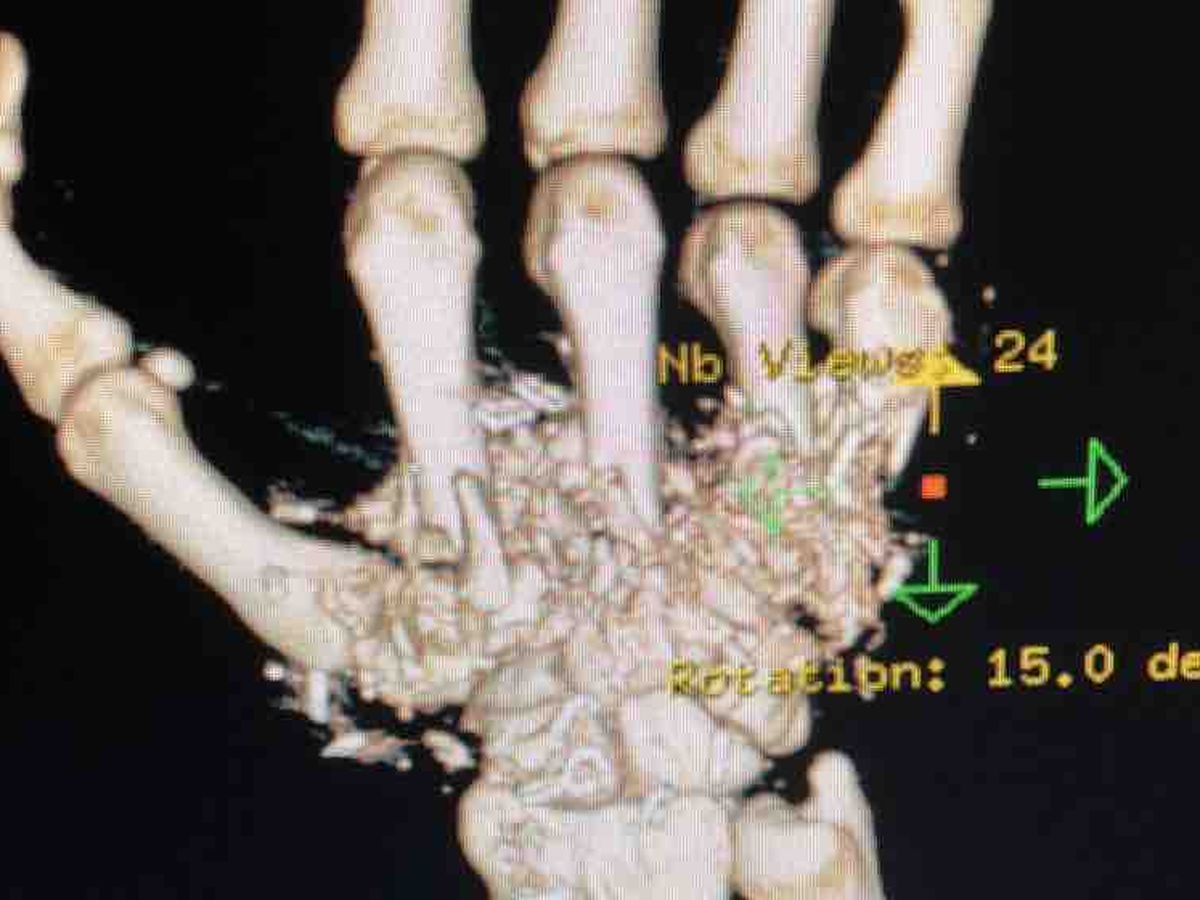

As many of you know Bryan had a devestating accident on January 21, 2018. He was in the hospital from January 21-26. He had 2 surgeries on his hand at that time. He went back to the Hospital on Tuesday February 13 to go have his skin graft done but when they put him on the operating table part of his hand wasn’t healing properly like the doctor was hoping it would. So the doctor told us to go to the emergency room at the same hospital that he had the surgery right away. They had to put a wound vac on his hand to help get blood flowing again to the part that isn’t healing properly. So now he is going to be in the hospital from February 15 to February 22. He got the wound vac put on yesterday and is going to have another surgery sometime next week before he goes home again. When he finally goes home after that surgery he will have a home nurse come and change it out for him 3 days a week. He could possibly have this wound vac on for up to 2 months and be out of work even longer. Once this wound vac comes off he will then have to have his skin graft done which will keep him out of work longer. Bryan had the accident when we returned home from hunting that weekend. He was bringing everything into the house and the zipper on his rifle case broke. As he went to open the garage door and he felt the gun slipping out of the case and his reaction was to grab it with his right hand but slipped out and hit the ground and set off the pin. The bullet went through his hand causing a lot of damage. It’s going to be a long recovery. He won’t be able to move his wrist again, but at least he will be able to move his fingers. We don’t like to ask for help but Bryan is the only breadwinner for our family and now that he’s out of work things are getting scary. We don’t have any idea when he’ll be able to return to work. Our lives have been turned upside down.